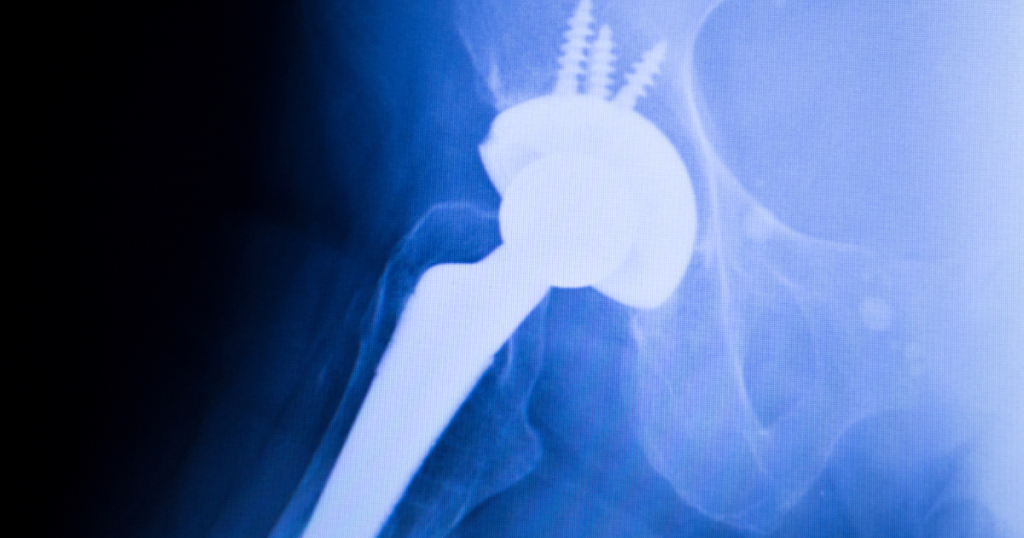

股関節の手術の痛みの残存率は〇〇%

股関節の痛みが股関節にない代表的な証明があります。

股関節痛を長年抱えていて改善されないと

股関節の手術を行います。

しかし…

股関節の手術の痛みの残存率は

3-4年後で40%

その中、強い痛みは15%

になります。

もし股関節の痛みが

股関節の問題で起きているのであれば、

これらの手術をして

股関節を正常な状態に戻せば

痛みは消えるはずです。

しかし、

股関節を正常に戻しても

痛みがこれだけ

残存してしまっているということは

「股関節の問題=股関節の痛み」ではない

ことを証明しています。

長年の股関節の痛みだからと言って容易に手術を選択することは控えましょう!